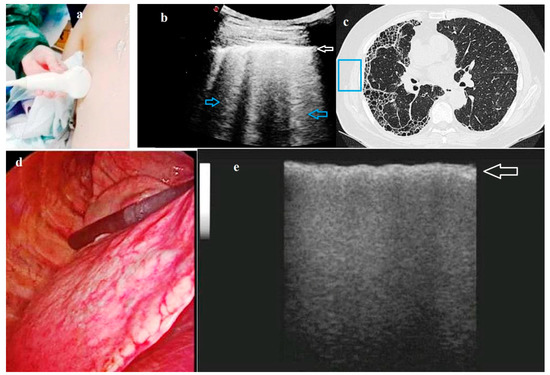

A systematic evaluation of the lung parenchyma without artifacts due to the elevated difference in acoustic impedance encountered by the ultrasound beam at the interface between the aerated lung parenchyma and the overlying soft tissues of the chest wall can be theoretically made possible by the ILU approach. As a confirmation, B-lines artifacts have been shown to be absent in ILU scans even in patients with pulmonary fibrosis, despite these ultrasound findings were observable at TUS examination in our previous experience [29] (Figure 4). During open thoracotomy, in which the ribs are spread, even the obstacle constituted by these bony structures is eliminated. As the probe is placed directly on the lung surface, high-frequency transducers can be used, affording much better resolution than the low-frequency transducers used for TUS.

Figure 4. A case of Usual Interstitial Pneumonia (UIP) fibrosis (histological diagnosis). (a) Photograph taken during the pre-operatory Transthoracic Ultrasound (TUS) examination showing a multi-frequency convex probe (2–8 MHz) placed on the posterior chest wall. (b) Pre-operatory TUS scan (convex probe, 5 MHz) showing an increased thickness of the hyperechoic pleural line (white arrow) and an increased number of B lines below it (blue arrows). (c) High-Resolution Computed Tomography (HRCT) scan of the same patient showing a pattern of fibrosis. The blue box enhances the area corresponding to the TUS scan showed in b). (d) Image of the pulmonary parenchyma during video-assisted thoracoscopic surgery (VATS). (e) Intraoperatory lung ultrasound (ILU) scan (linear probe, 12 MHz) showing an irregular thickening (white arrow) of the interface line between lung and the ultrasound probe (i.e., the intraoperatory “pleural line”) with no artifact below it.